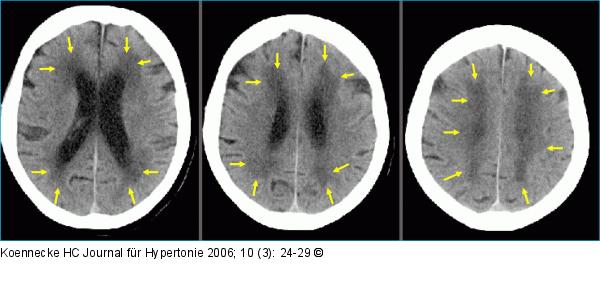

Abbildung 1b: Zerebrale Mikroangiopathie - Arterielle Hypertonie Zerebrale Mikroangiopathie infolge langjähriger arterieller Hypertonie. Sog. "Leukoaraiose" (weiße Rarefizierung) im CCT, erkennbar als teils konfluierende, teils fleckige Dichteminderung (Pfeile) der Marklager-Strukturen, wie sie häufig, aber keineswegs ausschließlich als Folge einer chronischen Hypertonie gefunden wird. Der Begriff ist rein deskriptiv und bezieht sich auf das pathoanatomische Korrelat mit diffuser Gliose und Atrophie des Marklagers. |

Abbildung 1b: Zerebrale Mikroangiopathie - Arterielle Hypertonie

Zerebrale Mikroangiopathie infolge langjähriger arterieller Hypertonie. Sog. "Leukoaraiose" (weiße Rarefizierung) im CCT, erkennbar als teils konfluierende, teils fleckige Dichteminderung (Pfeile) der Marklager-Strukturen, wie sie häufig, aber keineswegs ausschließlich als Folge einer chronischen Hypertonie gefunden wird. Der Begriff ist rein deskriptiv und bezieht sich auf das pathoanatomische Korrelat mit diffuser Gliose und Atrophie des Marklagers. |